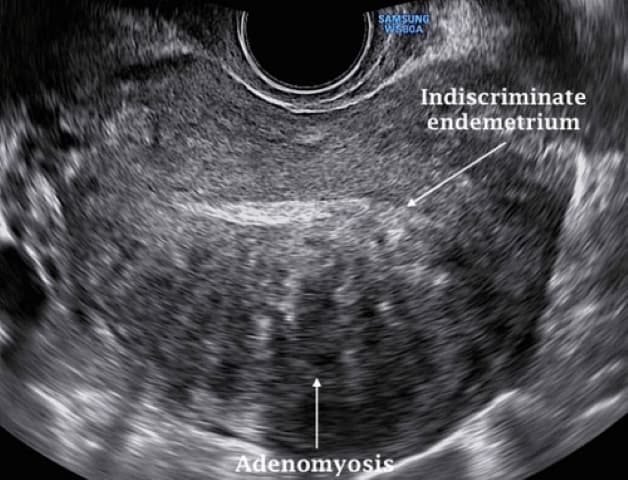

Hình ảnh siêu âm lạc nội mạc tử cung trong cơ tử cung

Bằng cách xâm nhập sâu thông qua siêu âm lạc nội mạc tử cung bằng đầu dò âm đạo đã thu về được nhiều ưu điểm nổi bật so với các công cụ hình ảnh học dùng để chẩn đoán khác. Theo đó, siêu âm có thể phát hiện được lạc nội mạc tử cung với độ chính xác cao. Lương mô càng lớn thì vị trí càng dễ quan sát. Mặc dù tổn thương càng lớn sẽ càng dễ nhìn thấy trên siêu âm thì với sự phát triển trong kỹ thuật siêu âm ngày nay và với các chuyên gia chẩn đoán hình ảnh có nhiều kinh nghiệm, chỉ cần có vài milimet mô lạc nội mạc tử cung trong cơ thể là đã có thể được chẩn đoán được. Tổn thương lạc nội mạc tử cung thể hiện trên màn hình siêu âm sẽ trông tối hơn (được xem là đen hơn) với các mô bình thường xung quanh.